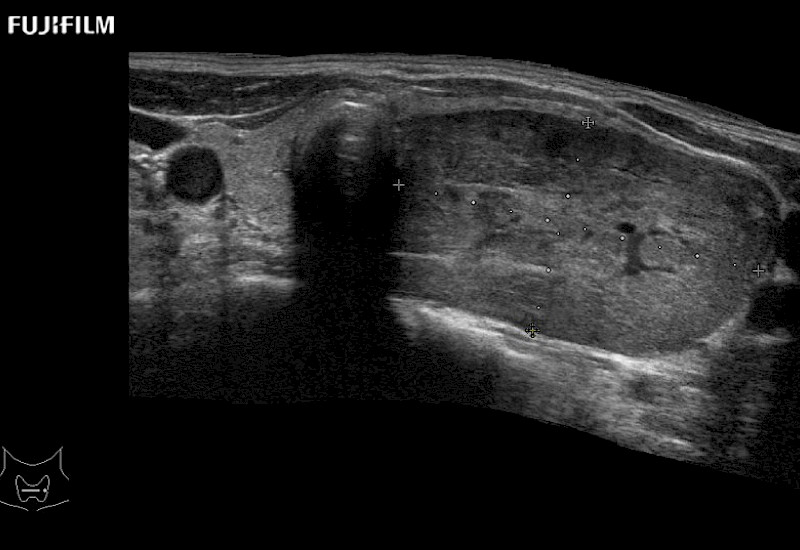

Linear array side-fire “T” transducer for open surgical procedures.